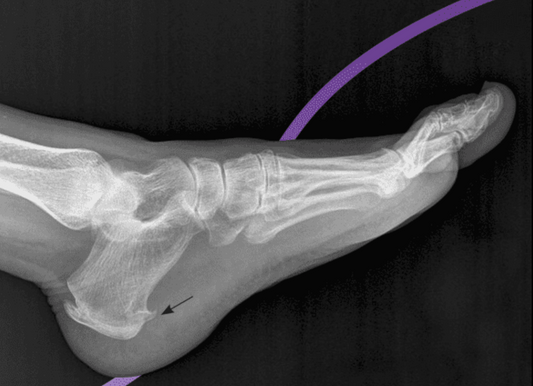

Read moreUnderstanding Heel Spurs: Symptoms and Causes

Heel spurs, or calcaneal spurs, can be painful and challenging to manage. Understanding the symptoms and causes of heel spurs is crucial for seeking appropriate treatment and relief from discomfort.

Read moreManaging Calcaneal Spurs: Treatment Options and Tips

Managing calcaneal spurs requires a comprehensive approach that includes rest, ice, stretching exercises, footwear modifications, orthotic devices, medications, injections, and possibly surgery. Consulting with a healthcare provider is crucial to...